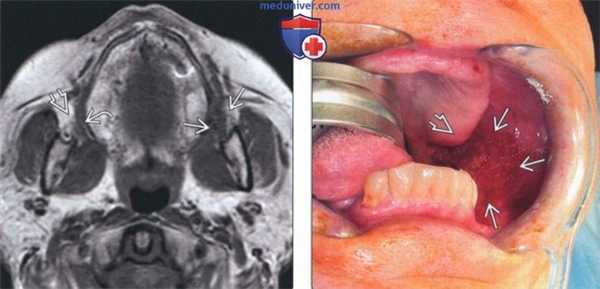

(Слева) На аксиальной МРТ (Т1 ВИ) визуализируется плохо отграниченная мягкая ткань, заполняющая щечную жировую подушку (глубокая инфильтрация клетчатки злокачественной опухолью слизистой оболочки щеки). Обратите внимание на ровные контуры щеки и «светлую» жировую ткань с другой стороны. В условиях, когда точное расположение первичной опухоли неизвестно, инфильтрация жировой клетчатки щеки может быть единственной едва заметной находкой.

(Справа) На фотографии у этого же пациента виден первичный ПКР слизистой оболочки щеки, расположенный вдоль заднего края внутренней стороны щеки, распространяющийся к заднему краю альвеолярною отростка верхней челюсти, не несущего зубы.